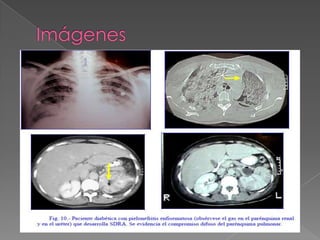

La respuesta pulmonar ante la injuria aguda es difusa e inespecífica:

Disnea aguda en un inicio hipoxemia, que no se corrige con el aporte

De oxigeno suplementario y la radiografía de tórax muestra el edema

pulmonar

 1.- Inicio agudo

 2.- Presencia de una afección

predisponerte

 3.- Infiltrados bilaterales en la rx de

tórax

 4.- PaO2/FiO2 < 200 mmhg